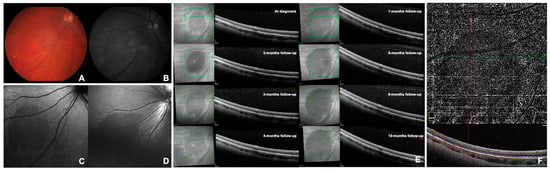

CASE 2. A 23-year-old Caucasian female was followed as an outpatient for recurrent anterior uveitis predominantly affecting the RE. The patient was affected by juvenile idiopathic arthritis in therapy with methotrexate, certolizumab pegol and topical dexamethasone in the RE. BCVA was 0.0 logMAR (20/20) in both eyes (spherical equivalent: −4.00 diopters in RE and −4.25 diopters in LE). A 0.5+ grade of anterior chamber cells (SUN grading) was noted in the RE with no other clinical signs of uveitis. The anterior segment examination of the fellow eye was unremarkable. The fundus examination of both eyes appeared within normal limits except for an oval-shaped dark spot of approximately 4 papillary diameters in the inferior nasal mid-periphery of the LE diagnosed as DWP (Figure 1A). The lesion was more evident by red-free light ophthalmoscopy and was hypo-fluorescent on BAF and hypo-reflective at NIR and BR examinations (Figure 1B–D). At the OCT scans, the dark area corresponded to an attenuation of the EZ (Figure 1E). At OCT-A, the en-face examination of the outer retina showed a decrease in the projection artifacts usually present in this normally avascular slab when using this device. This effect became even more evident by manually setting the upper and lower limits of flow detection, including only the EZ band (Figure 1F). The superficial and deep capillary plexus and the choriocapillaris did not appear to be affected. The visual field examinations with 60-4 and 30-2 SITA-SAP were within normal limits. The scotopic ERG of the RE was “slightly” reduced in amplitude, whereas all ERG findings of the LE were within normal limits. At follow-up visits, we documented a constant monthly increase in lesion diameter by OCT (Figure 1E) in the absence of visual symptoms. FA showed the presence of late papillary leakage with peripheral vasculitis in the RE and only mild generalized blood–retinal barrier breakdown in the LE. The DWP lesion was silent both at the FA and ICGA; the latter exam was unremarkable in both eyes throughout the entire examination.

Figure 1. Selected images of dark without pressure from Case 2 (see text). Panel (A) shows the color retinography during the 3-month follow-up examination. Panel (B) shows the red-free retinography during the 3-month follow-up examination. Panel (C) shows the blue autofluorescence at the time of diagnosis. Panel (D) shows the blue reflectance during the 3-month follow-up examination. Panel (E) shows infrared optical coherence tomography at the time of diagnosis and the subsequent follow-ups. Panel (F) shows the optical coherence tomography–angiography with the flow limits set at the ellipsoid zone level at the time of diagnosis.